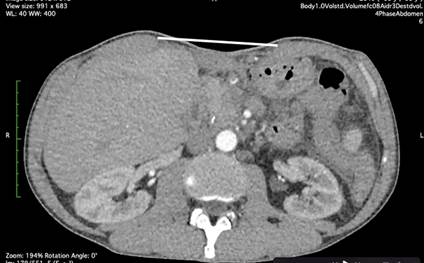

Выполнена операция TAR с имплантацией стандартной полипропиленовой сетки 30х30 см. Этапы вмешательства соответствовали общепринятым для задней сепарации [5]. Осуществлена профилактика инфекций области хирургического вмешательства (ципрофлоксацин 400 мг внутривенно перед вмешательством и далее 2 раза в сутки) и венозных тромбоэмболических осложнений (эноксапарин 0,4 мл подкожно 1 раз в сутки). Активизирован в 1-е сутки после операции. На 5-й день отмечена лихорадка до 39 ºC. Уровень C-реактивного белка 347 мг/л. Тест на COVID-19 отрицательный, на фронтальной рентгенограмме легких инфильтративных изменений нет. Терапия препаратом имипенем/циластатин оказалась совершенно неэффективной. На КТ обнаружены большие жидкостные скопления с пузырьками газа, расположенные ретромускулярно и в ране (рис. 9).

Рис. 9. КТ второго пациента после операции. Белой стрелкой показано жидкостное скопление с пузырьками газа в ране, зеленой стрелкой показано жидкостное скопление с пузырьками газа в ретромускулярном пространстве

Во втором клиническом случае для оценки ситуации была применена КТ, которую следует расценивать как наиболее эффективный метод диагностики [6, 20, 21]. Однако трактовка результатов вполне могла быть иной. Жидкостные скопления в послеоперационном периоде обычно рассматриваются как абсцессы (если есть системная воспалительная реакция), гематомы или серомы (если признаков воспаления нет) [6, 20]. В большинстве случаев наличие обширных жидкостных скоплений с пузырьками газа с признаками системной воспалительной реакции является аргументом к немедленной ревизии раны. В данной ситуации включения газа расценены как остатки воздуха в ране после операции. Клинически заподозрена MRSA-инфекция, далее с помощью целевой антибиотикотерапии все имеющиеся проблемы были решены без пункций и вмешательств. Данный пример демонстрирует возможность и эффективность консервативного подхода к лечению воспалительного осложнения.